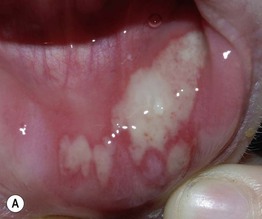

– Initial lesions: small round vesicles on an erythematous base; often painful or burning; the grouping of these vesicles is a clue to the diagnosis; vesicles may become umbilicated or pustular, followed by erosions or ulcerations with hemorrhagic crusts, often with a scalloped border; lesions resolve over 2–6 weeks (Fig. 67.1).

Fig. 67.1 Primary herpes simplex virus (HSV) infections. A Primary herpes gingivostomatitis due to HSV-1 in a child. Note the coalescing lesions with scalloped borders. B HSV-2 infection in a teenager (primary vs. non-primary initial infection). Note the scalloped borders. C Primary genital HSV infection. In addition to 1- to 2-mm hemorrhagic crusts, there are perifollicular vesicopustules. A, Courtesy, Julie V. Schaffer, MD; B, Courtesy, Jean L. Bolognia, MD; C, Courtesy, Stephen K. Tyring, MD.